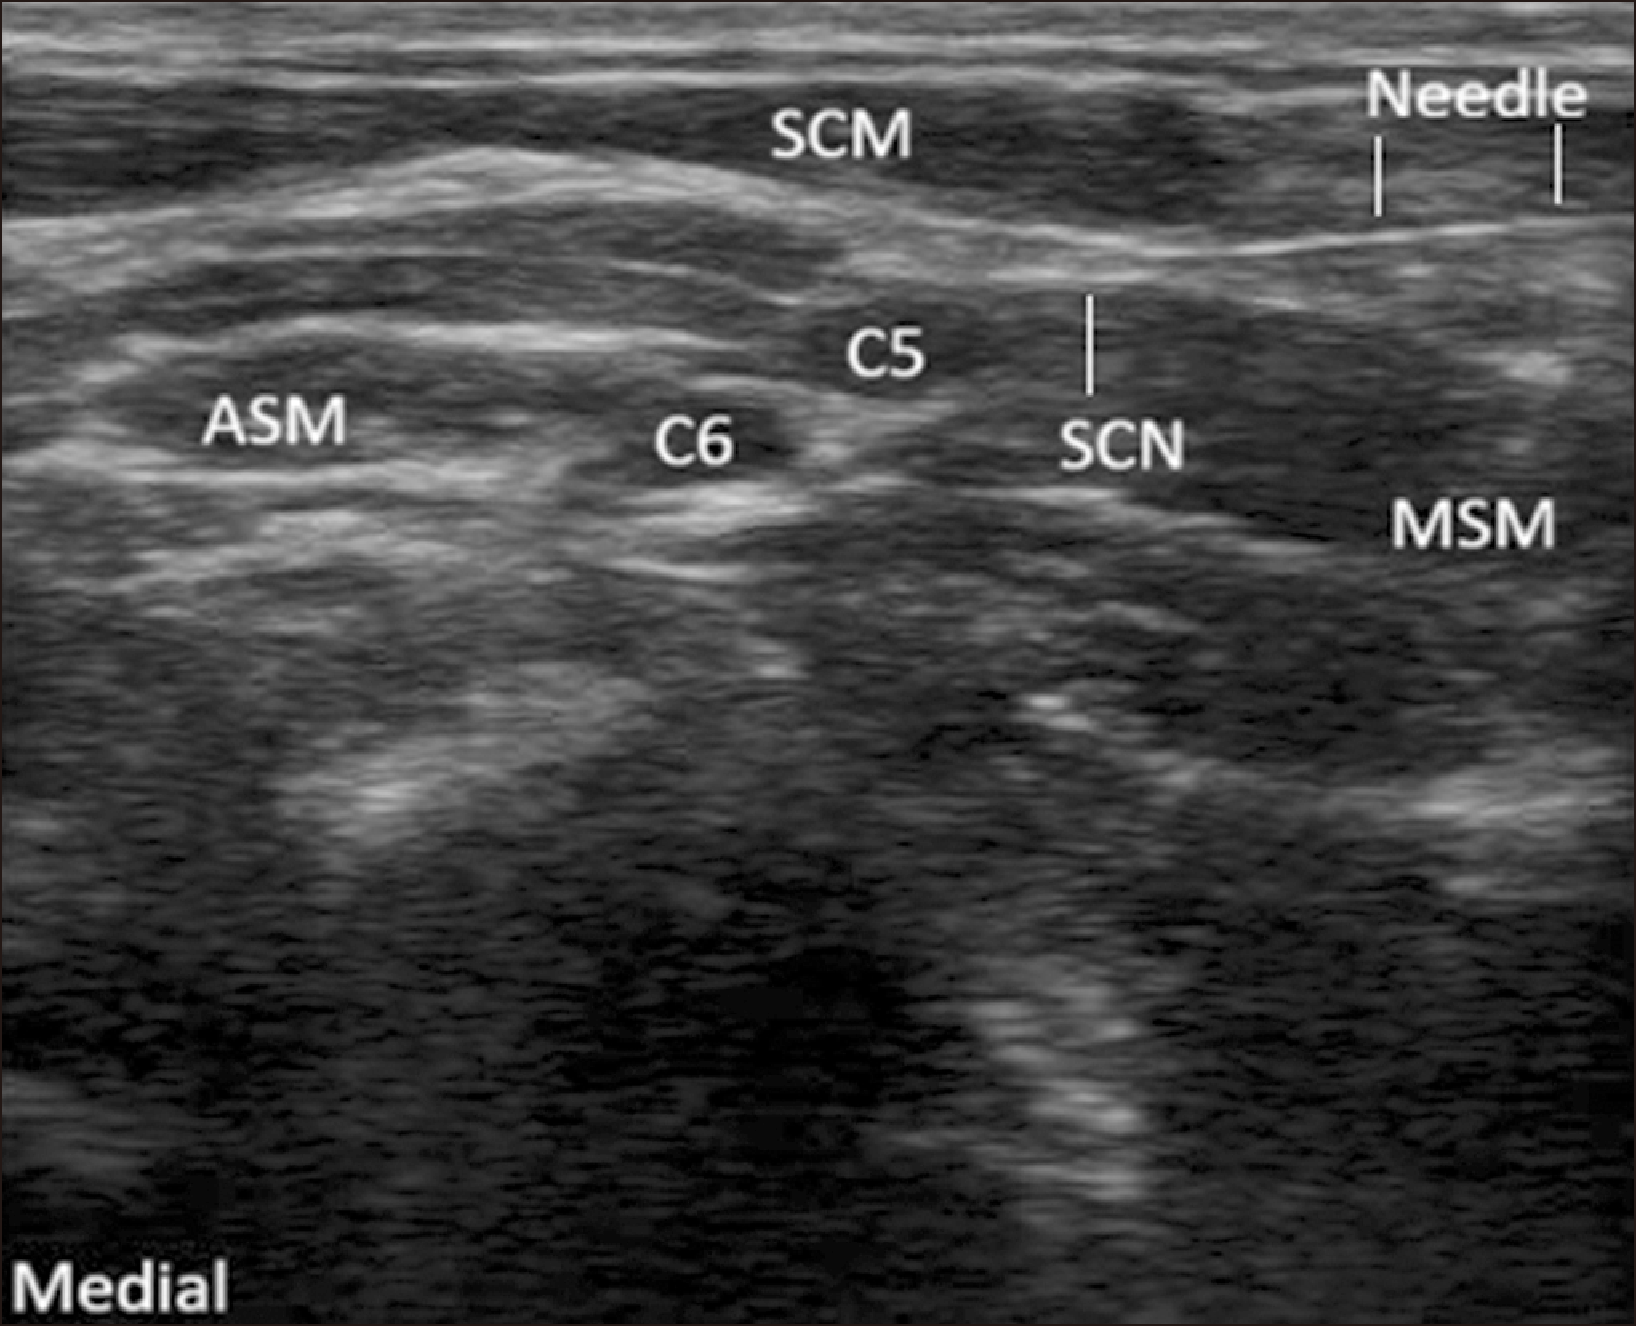

After performing the SCN block, the needle was advanced in a caudal to cranial direction to inject 15 mL of local anesthetic mixture in 0.5 mL aliquots beneath the clavipectoral fascia in order to separate it from the periosteum of the clavicle [12]. The injection was administered at both ends of the clavicle, with 7.5 mL injected on each side (Fig. 3).

Fig. 3

Ultrasonographic image of the CFP block. The needle is advanced in a caudal to cranial direction. CFP: clavipectoral fascial plane, Pec major: pectoralis major muscle, Subclavius: subclavius muscle, CPF: clavipectoral fascia.